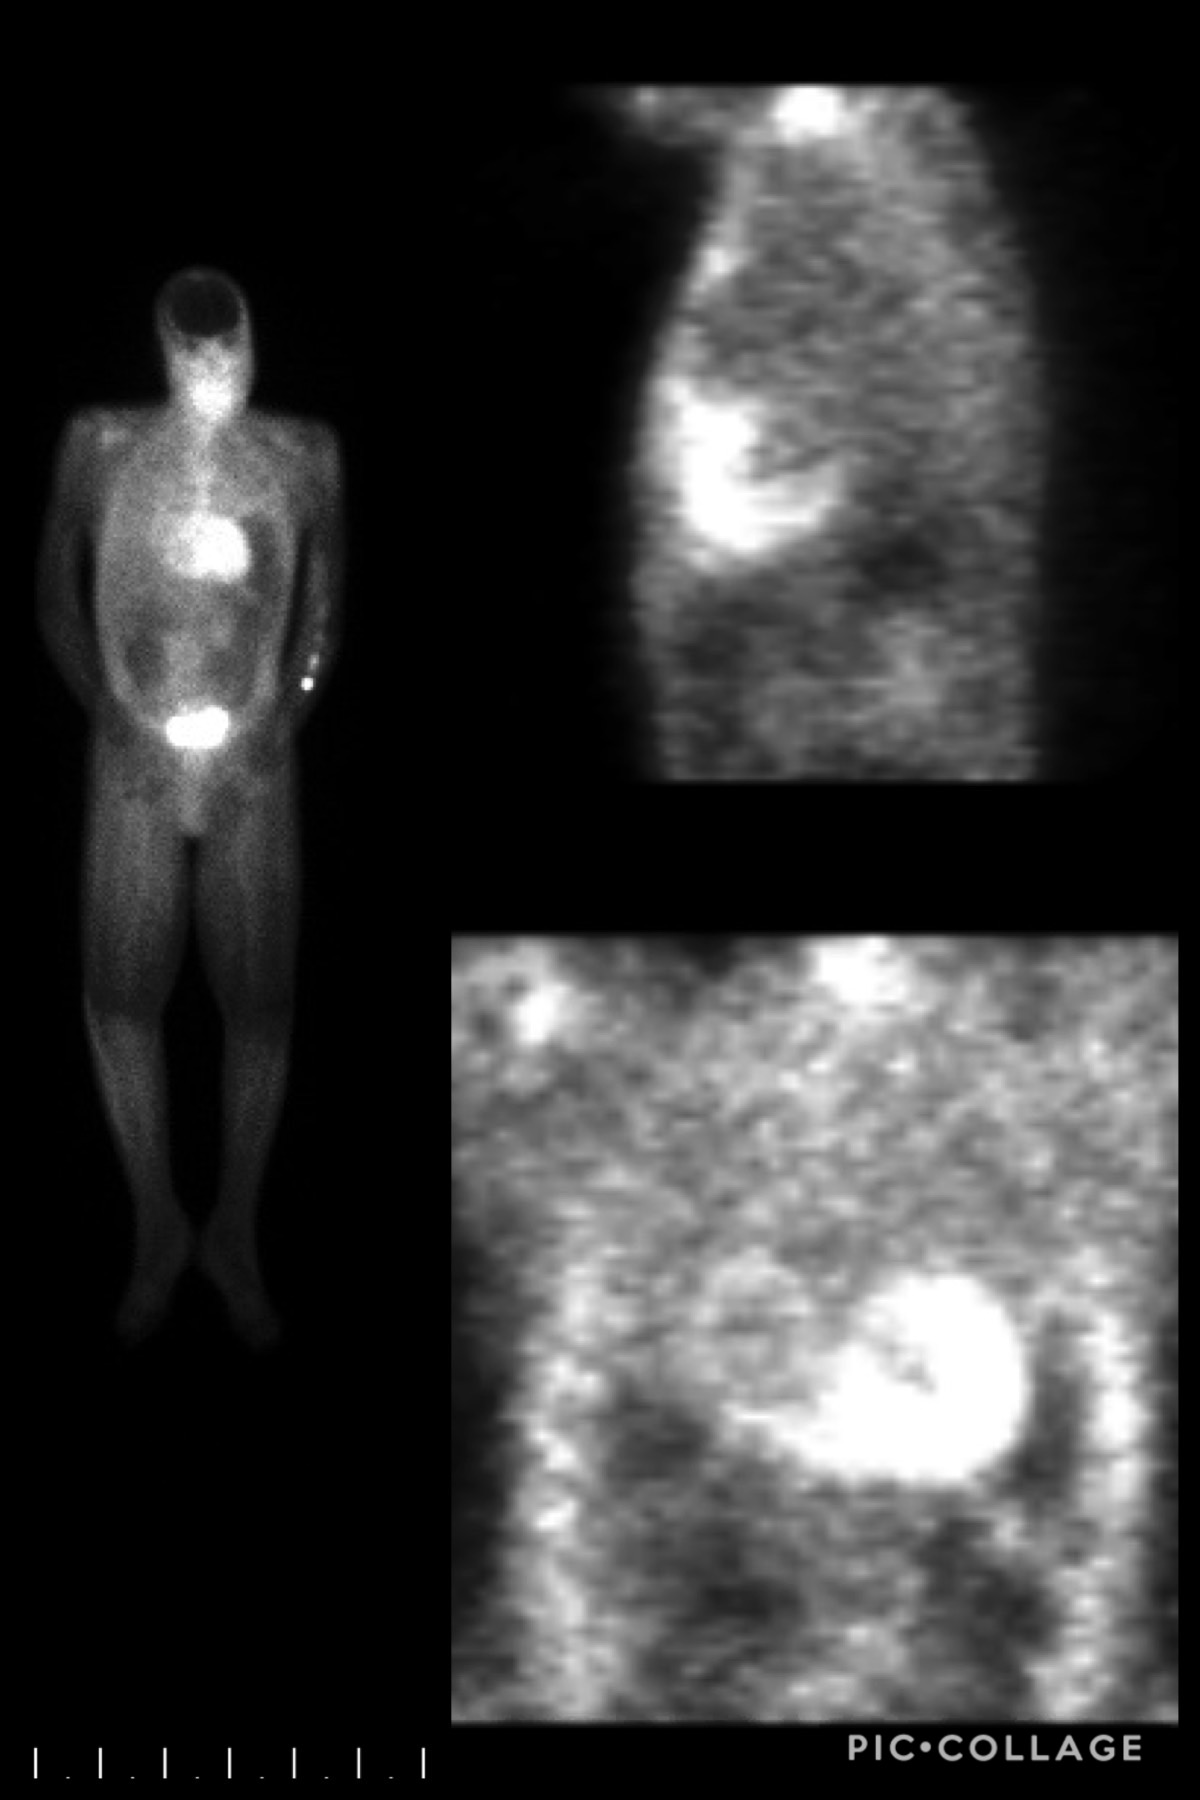

Transthoracic echocardiography (ECHO) was obtained which revealed a progressive decline in left ventricular ejection fraction (LVEF) to 25-35% along with worsening diastolic dysfunction with E/A 3.5 and medial E/E’ 24 despite patient’s adherence to medical management. ECHO at HF diagnosis (3-years prior) showed LVEF 50-55% and mild diastolic dysfunction E/A 0.78. Repeat ECHO 1.5 years prior revealed a decline in LVEF to 30-40%. Cardiac MRI was performed to rule out apical ventricular thrombi and showed diffuse late gadolinium enhancement concerning for amyloidosis. Follow up nuclear bone imaging revealed increased cardiac uptake greater than bone, suggestive of grade III cardiac amyloidosis. Fat pad biopsy and mass spectrometry confirmed tissue transthyretin amyloidosis. The patient was managed conservatively with diuretics and discharged with appropriate follow ups in place. His home lisinopril and metoprolol were discontinued due to concerns that they may worsen amyloidosis symptoms.